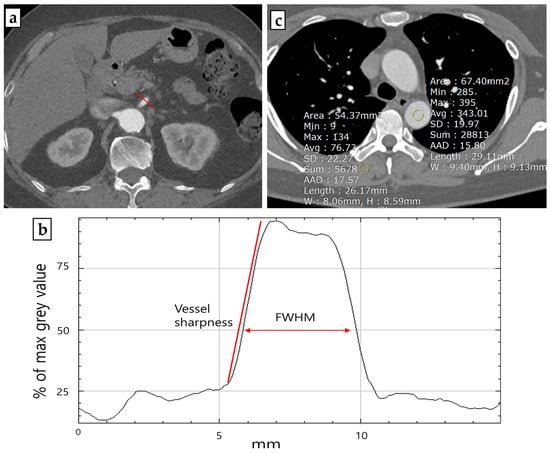

The demographic characteristics of the study population and radiation dose estimates are presented in Table 2. There were no significant differences between the two cohorts in terms of age (p = 0.583), sex (p = 1.000), or BMI (p = 0.857). However, the CT findings for TACTA varied significantly between the groups (p = 0.001). Notably, there were various findings, such as aortic aneurysms, acute aortic syndromes, and cases requiring postoperative follow-up after aortic surgery, which necessitated the scans. In the TF100kV group, two cases following EVAR procedures exhibited endoleaks, and two cases necessitated emergency TEVAR due to thoracic aorta dissection (Figure 2).

The pivotal findings of our retrospective study highlight that using Sn 100 kVP is comparable to standard protocols in diagnosing aortic or arterial diseases and preoperative planning. This comparability considers objective parameters, dose exposure, and clinical implications. In our cohort, 40% of patients undergoing either endovascular or surgical repair for acute aortic syndrome encountered no challenges in postoperative assessments, such as detecting endoleaks, even when TACTA with a TF was used. Prior studies also confirm the efficacy of TF in reducing metal artifacts without degrading image quality or increasing the dose [18]. These benefits are particularly significant in postoperative vascular lesion assessments, even in the presence of stents or stent grafts (Figure 3).

Figure 3. Examples of third-generation dual-source computed tomography clinical applications include Sn100 spectral shaping in a patient with a type II endoleak following endovascular aneurysm repair (EVAR). After EVAR for an abdominal aorta aneurysm, there appeared to be contrast media leakage inside the aneurysm sac, suggesting an endoleak (a). The patient was suspected to have an accompanying aneurysmal sac rupture and thus underwent embolization. During aortography, contrast leakage was observed in the delayed phase (b). This seemed to originate from the right iliolumbar artery, and embolization was performed using Onyx after selection (c). A follow-up was conducted two days later using the Sn100kV protocol, where the radiopaque Onyx was visible, and no further contrast media leakage was observed (d).